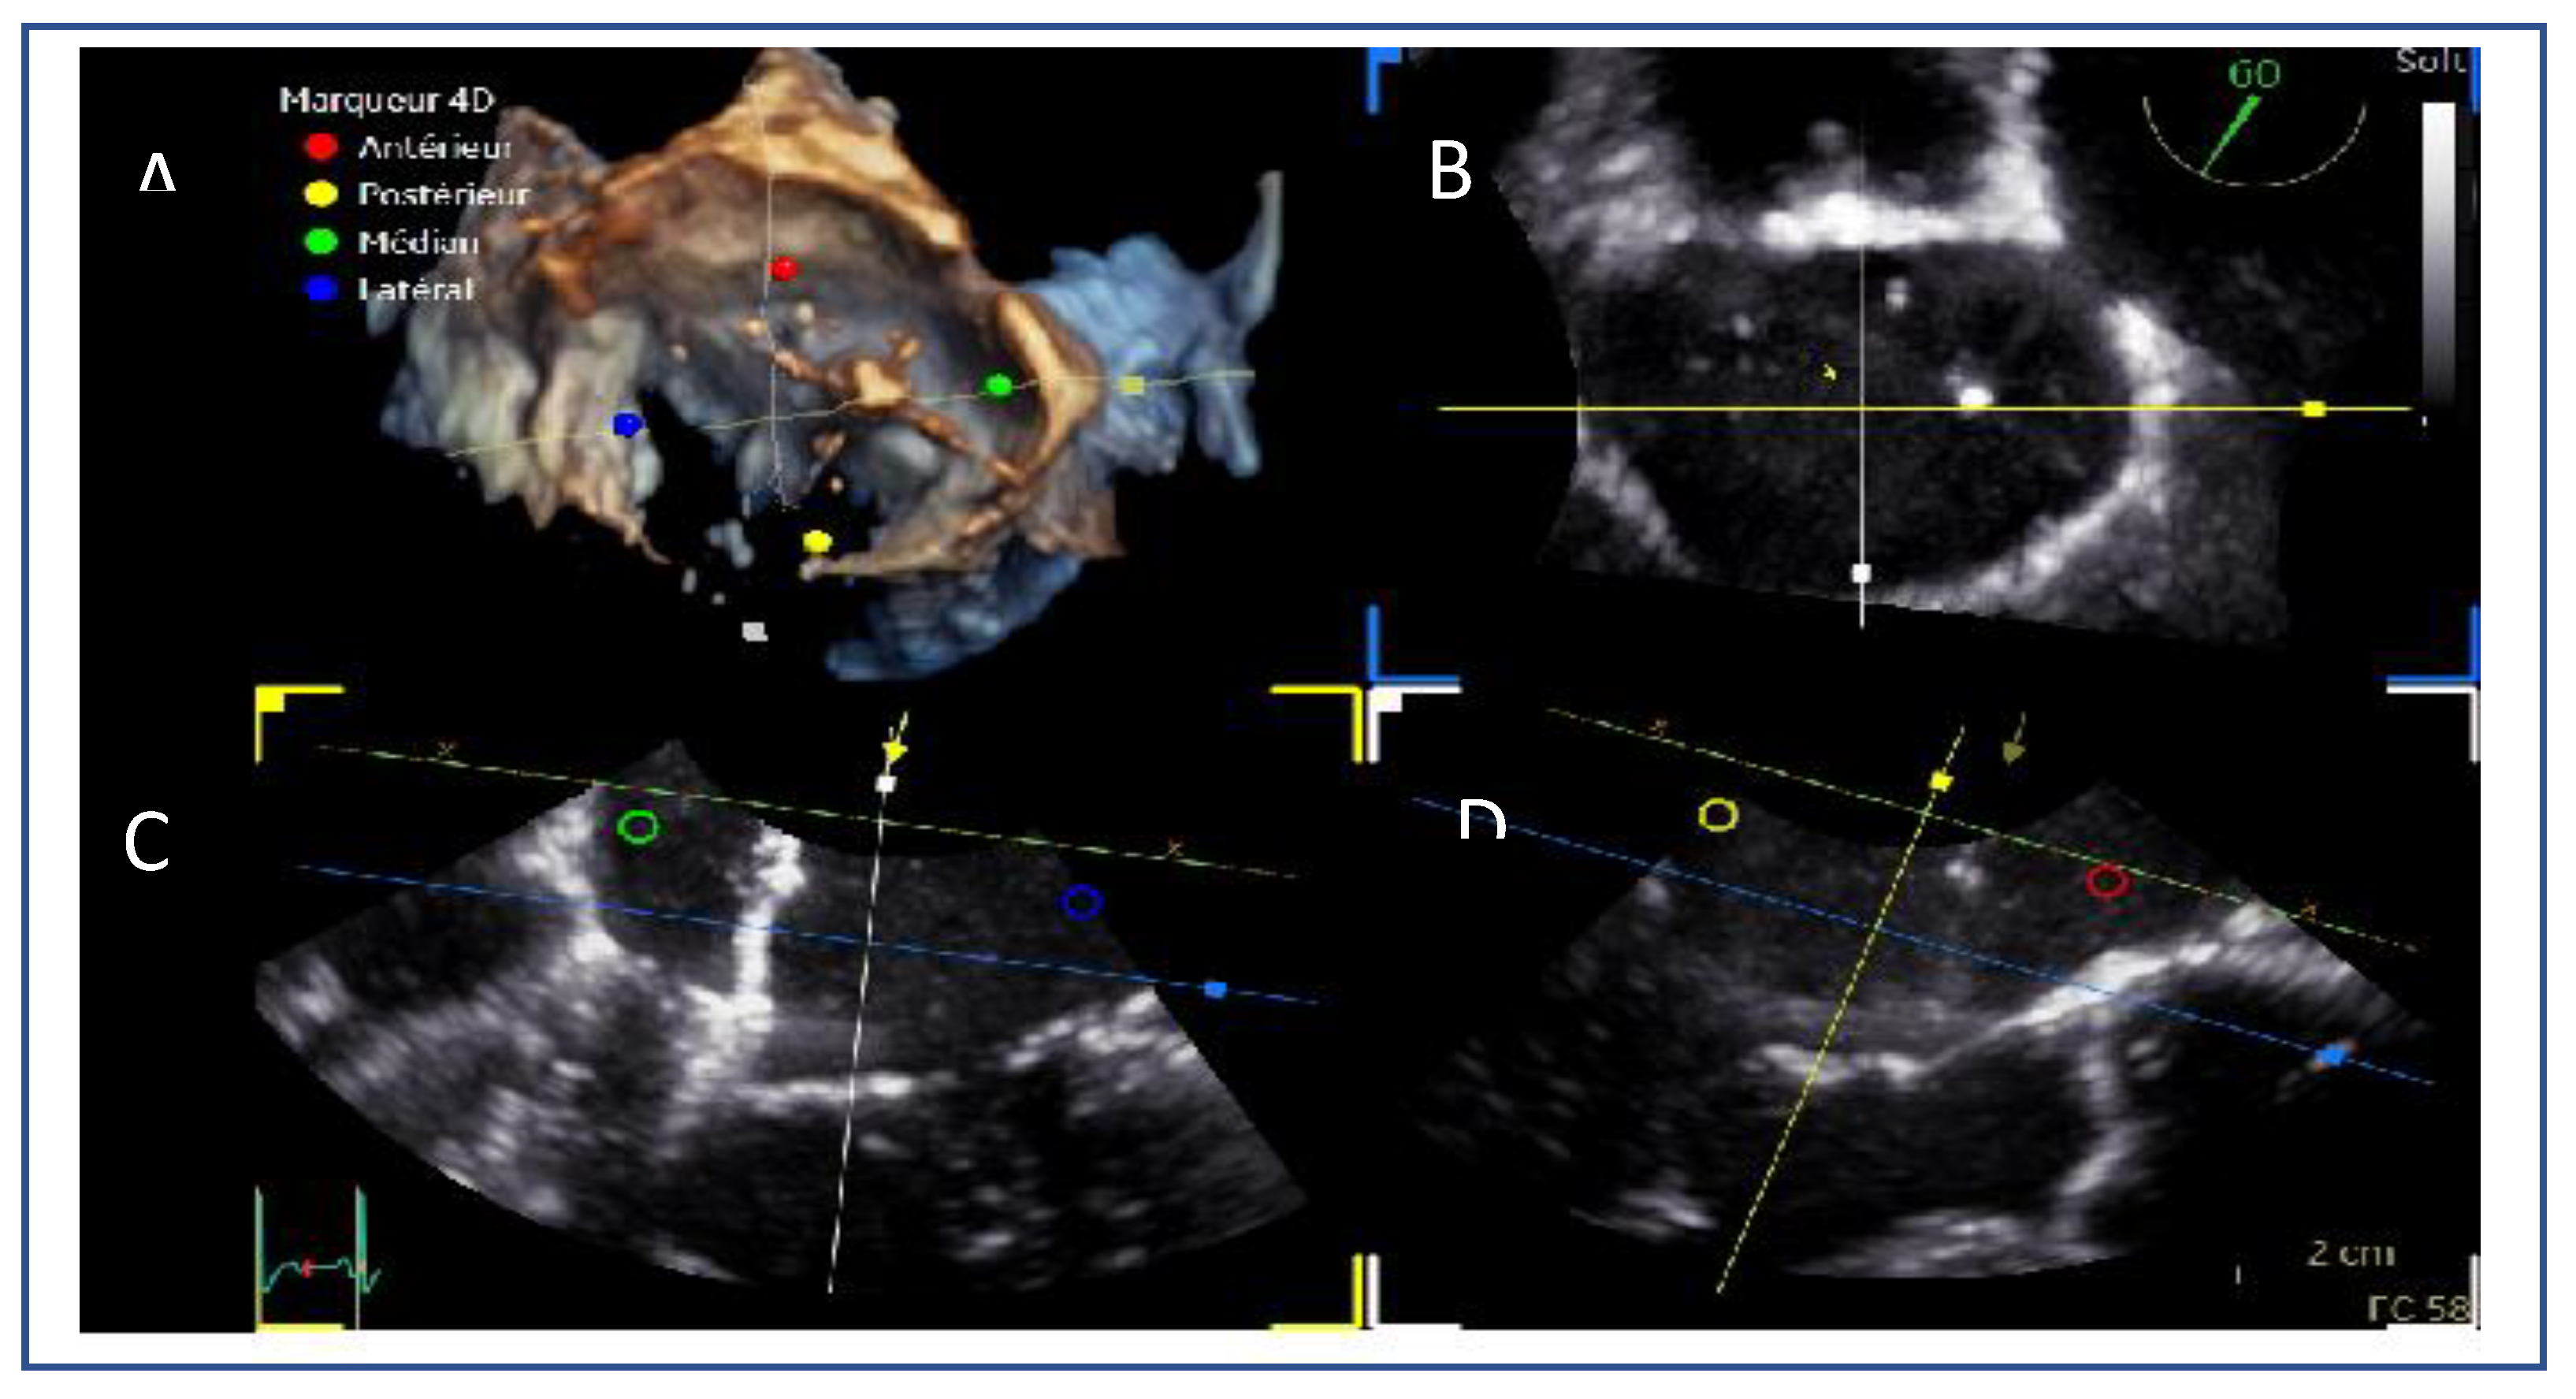

- Lateral commissure: A superior and lower puncture height, approximately 3.5 cm, is preferred to facilitate access.[40]

- Medial commissure: A more inferior puncture, closer to the inferior vena cava (IVC), with a higher height of 4.5–5 cm is recommended for better alignment. [41]

- Ventricular functional MR: The puncture height should be set 1 cm lower than the usual height to match the coaptation depth.[40]